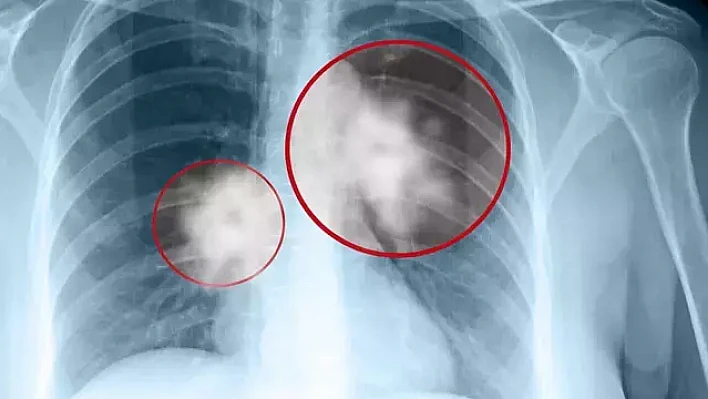

Erken evre tümörler LDCT ile tespit edilebiliyor

LDCT’nin düşük radyasyon dozu ile akciğerleri yüksek çözünürlükte görüntüleyen özel bir tarama yöntemi olduğunu belirten Katgı, şu bilgileri paylaştı:

Klasik toraks BT’de radyasyon dozu 6–7 mSv iken LDCT’de 1–2 mSv civarındadır. Yani 3–5 kat daha düşük radyasyonla ayrıntılı görüntü elde edilir. ABD’de yapılan NLST çalışması, LDCT taramasının akciğer kanserine bağlı ölümleri yüzde 20 azalttığını göstermiştir. Avrupa’da yapılan NELSON çalışması da benzer sonuçlar ortaya koymuştur.”

Bu verilerin, erken evre akciğer tümörlerinin LDCT ile yakalanabildiğini kanıtladığını ifade eden Katgı, LDCT’nin güvenle uygulanabilen, ağrısız, kısa sürede tamamlanan ve kontrast madde gerektirmeyen bir yöntem olduğunu vurguladı.